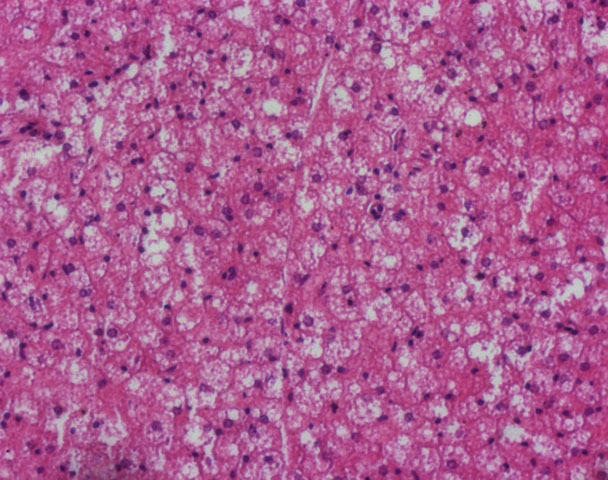

Un’immagine del tessuto adiposo bruno (BAT) caratterizzato da cellule di piccole dimensioni contenenti più gocce lipidiche e di piccole dimensioni (sono quelle goccioline bianche che si vedono in mezzo alla generale colorazione rosa; i nuclei sono quelli con una colorazione più scura. La colorazione è eosina-ematossilina). Credit: "Giovanni Galli” Laboratory.